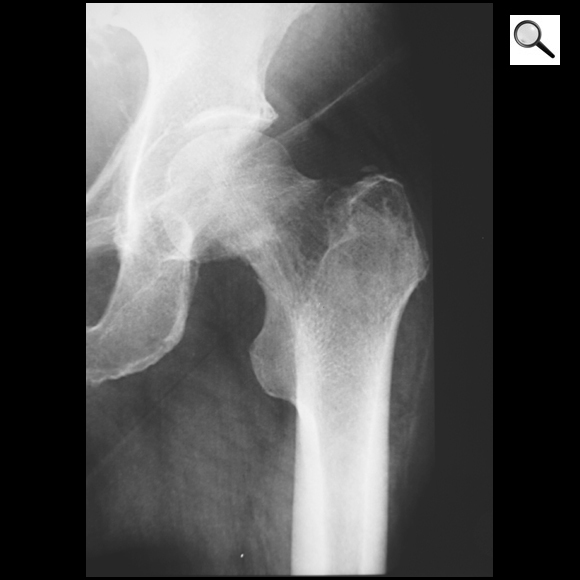

Quel est le stade Garden de cette fracture du col?

Fracture ES fémur gauche Garden 2 car pas déplacé et travées osseuses non déformées

! risque de déplacement secondaire !